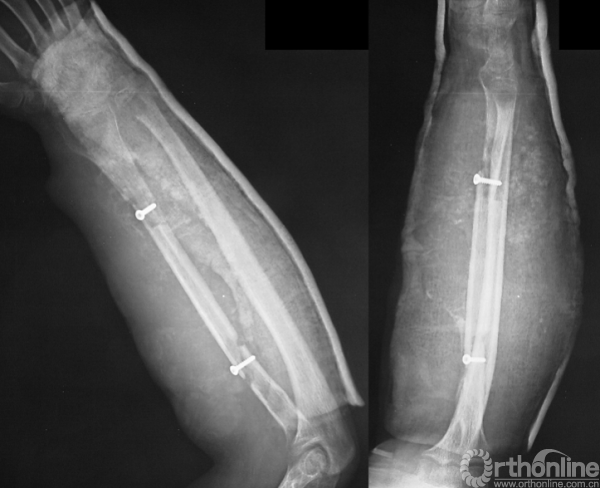

于当地医院就诊,诊断为“病理性骨折”,在未行术前活检的情况下,行“瘤段切除、腓骨移植术”。术后病理示“浸润灶和新生软骨、未见恶性肿瘤成分”。临床据此未予进一步治疗,随诊。

图14-2 术后X线平片正侧位

图14-3 术后2月X线平片正侧位

图14-4 术后3月X线平片正侧位

图14-5 术后3月平扫CT

1.病理骨折诊断成立,但肿瘤性质未明确。以病史来看,短时间内出现复发,临床考虑侵袭性肿瘤可能性大,但病理并不能给予足够支持。这种情况可见于取材区域的不典型性或病理医生对骨肿瘤病理的认知不足。

2.仍然应该进行细致的影像学检查如局部加强CT来判断肿瘤的侵犯范围。